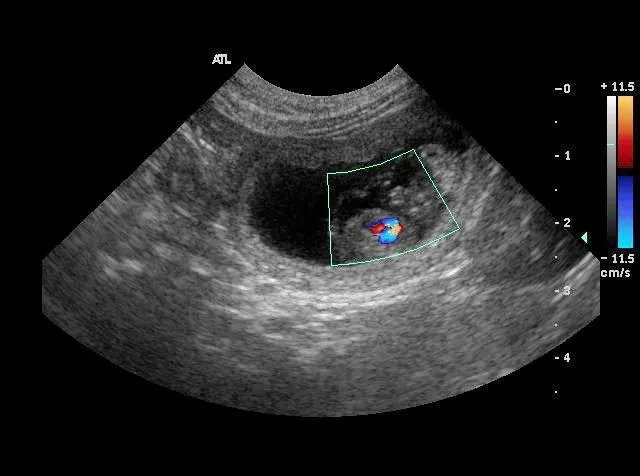

Cytology of the vulvar discharge (Figure 4A) revealed purulent discharge with numerous toxic neutrophils, intra- and extracellular bacteria, and parabasal vaginal mucosal cells. No cardiac motion was detected on abdominal ultrasonography of 7 nonviable fetuses (Figure 4B). Cardiac motion (Figure 4C) was shown on Doppler imaging of a viable fetus.